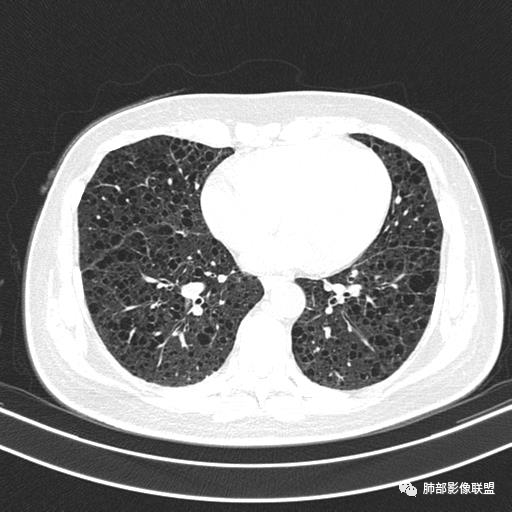

双肺弥漫囊腔,累及肋膈角,囊腔形态相对规则单一。

CT平扫示双肺弥漫分布大小不等囊状薄壁透光区,无内、中、外带分布差异,间质稍示增厚。拟LAM

中年女性育龄期妇女,咳嗽气喘,无吸烟史,有苯吸入史。影像:双肺弥漫均匀小囊腔,无明显分布优势,囊腔形态欠规则,壁薄,部分囊腔边缘血管征,伴双肺弥漫磨玻璃影,无结节,考虑lam,鉴别苯中毒肺损伤,囊腔多有分布优势,小叶中心分布为主,形态规整等

女,46,活动性气喘1年。苯吸入史半年。胸部CT:两肺弥漫囊腔,上至肺尖,下至肋膈角,形态类似小囊腔。考虑:LAM,鉴别LIP,BHD,PLCH等。

双肺弥漫大小不一薄壁含气囊腔,囊间肺组织正常,正常肺背景,肺尖肺底受累;青年女性,气喘,支持LAM

双肺多发大小相近的囊状影,分布趋势趋于一致,中年女性,考虑LAM。部分囊内见血管及分隔影,小叶中心性肺气肿代排

CT表现:双肺弥漫大小不等的薄壁囊腔,囊壁<2mm,外形规则,血管影多位于囊腔周围,囊腔之间肺组织正常,随着疾病进展到晚期,囊腔变大、增多,不可胜数,囊腔可融合成较大的囊,与肺气肿相似,形成间质性肺纤维化。部分病例可出现结节影。